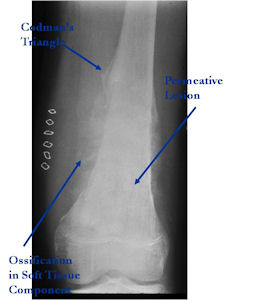

Aggressive Osteoblastoma vs. Osteosarcoma

Osteosarcoma:

- Cellular atypia

- High mitotic rate

- Atypical mitotic figures

- Abundant lacelike osteoid

- Permeative growth into adjacent bone and soft tissue

- Presence of neoplastic cartilage

- No peripheral shell of reactive bone

- Osteoblastomas that are greater than 4 cm and that show prominent periosteal new bone formation may present problems in differentiation from osteosarcoma

- May have foci of lace-like osteoid, high cellularity and more than a few scattered mitotic figures but these characteristics usually occur independently in an osteoblastoma vs all these atypical characteristics being present in an osteosarcoma